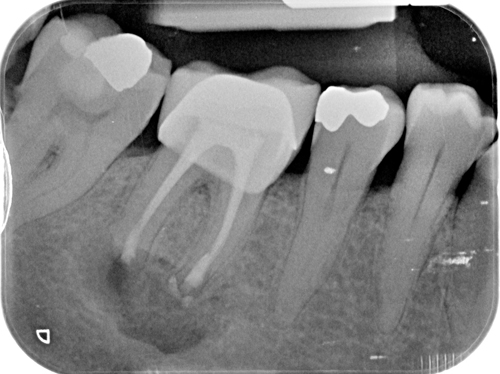

Nuestro paciente Eduardo Vicente Pedrós ha tenido en varias ocasiones infecciones en dientes que estaban desvitalizado. Él nos explica perfectamente en el vídeo que la cirugía periapical (o apicectomía) es un tratamiento que permite salvar la mayoría de los dientes afectados de esta patología.

Es una intervención técnicamente exigente, que requiere formación e instrumentos especializados (microscopio, endoscopio, etc.), pero que correctamente realizada no causa molestias prácticamente y tiene unos resultados exitosos en más del 90% de los casos.